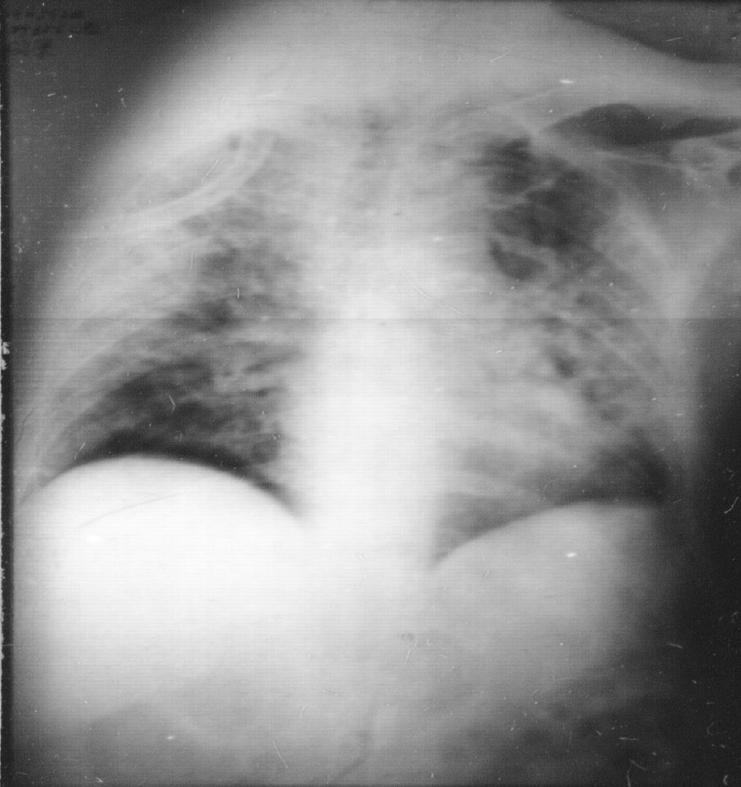

病灶分布: 糖尿病患者、用激素治疗的患者,肺叶分布差异不明显,而非「多为上叶尖后段、下叶背段」这类具有特征性的变化。所以,即使遇到下叶前段病灶时,也不能排除结核。

通常情况下,肺结核的 形态学特点 是多种形态共存,因为结核病病理生理发展的不同阶段可以在一个患者的影像学表现上同时存在,我们能看到渗出性病灶、增殖性病灶,甚至有纤维结节性病灶的改变。但免疫功能低下的宿主却缺乏多形特征,常呈均匀一致片状浸润。

免疫功能低下的人出现 肺内播散、肺外播散 的概率要更高。当患者免疫功能低下时,除了肺结核,我们也要想到会不会并发脑膜炎、椎旁脓肿?会不会出现脊柱结核、肝脏结核甚至盆腔结核?毕竟免疫功能被抑制后,病灶不会局限在一个部位。

此外,免疫功能低下的患者 空洞 相对少见、 胸腔积液 相对多见。